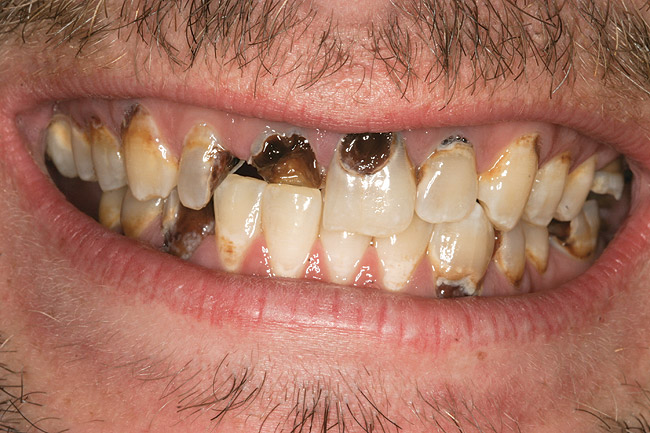

Figure 5  PRESENTATION CONDITION By the time Joe presented for treatment after serving time in prison and going to rehab, his teeth were completely destroyed by rampant decay. Although some teeth could have been saved, the patient chose to have all of the remaining teeth extracted in order to receive a set of full dentures.

Figure 5

Joe soon learned how to manufacture the drug. His need for meth soon consumed his every thought. He basically lived to do more meth. He admitted that he had made some poor choices. Unfortunately once the addiction kicked in, he no longer had a choice, he had to use. This was his end result (Figure 4 through Figure 6). From these photographs, one might think that he had used the drugs his entire life; however, this progression happened over the course of only about 1 year of smoking the drug. Because of the caustic chemicals (muriatic acid, hydrochloric acid, lithium, etc) his teeth started to blacken, then break.

Through all of this, there were no trips to the dentist. He knew his teeth were a mess, but he did not care. His addiction had such a hold on him that the only thing that he had to do every day was to get high. The addicted mind lowers a person’s values. It “hijacks” the brain to justify and rationalize why doing more meth is the most important reason for existence.

When Joe was finally arrested, his teeth were in the state seen in Figure 4 through Figure 6. He entered rehab, then served his time in prison. He received no dental treatment in prison. Once he was released on probation, he found it quite difficult to find a job. He was hired as a mechanic but only allowed to work in the garage. He was to have no contact with the customers because his appearance was hideous. His self-esteem was at the lowest point it could be. He felt better in prison. At least there, his prison mates understood why his teeth looked the way they did; many people in prison are there as a result of a chemical dependency issue.

As a new patient, Joe was instantly likable. He had a great sense of humor. He regretted how his life had turned out. When he finally presented to this author’s practice he was 24 years old. He wanted to remove the evidence of his addiction that were visible to anyone that came in contact with him. His teeth were totally destroyed by his drug use. There was no hope of saving any of them. There were horrible infections in his jaw bones that were spreading through his system. His only option was to remove all of his teeth and have dentures made. Impressions were taken with alginate. A bite was established in maximum intercuspation. We decided that his preoperative incisal edge positions of teeth Nos. 9 and 10 were adequate to recreate the incisal edge position in full dentures.